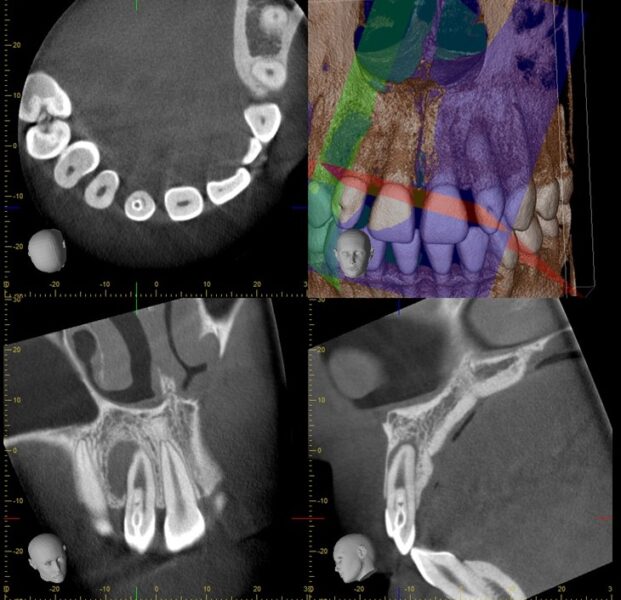

CTでも同様に骨欠損が認められ、歯内歯形態を示しています。

【術中マイクロ写真ならびに術中レントゲン写真】

根管内を拡大視野で確認し、出来る限り歯の切削量を減らすように治療をしています。

根の外側と内側から根管口という入り口があり、2本入っているのが分かります。また、この2本の根管は合流しており複雑な形態を示していることが分かります。